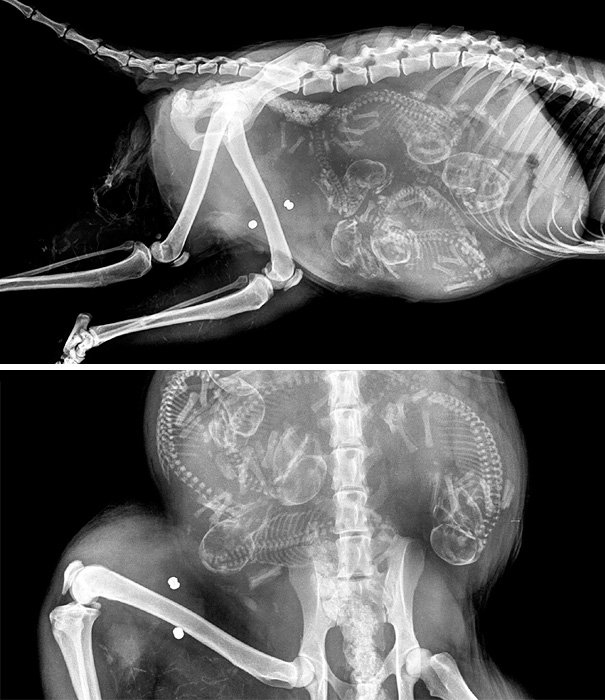

Итак, как выглядят рентгеновские снимки беременных животных:

кошка

собака